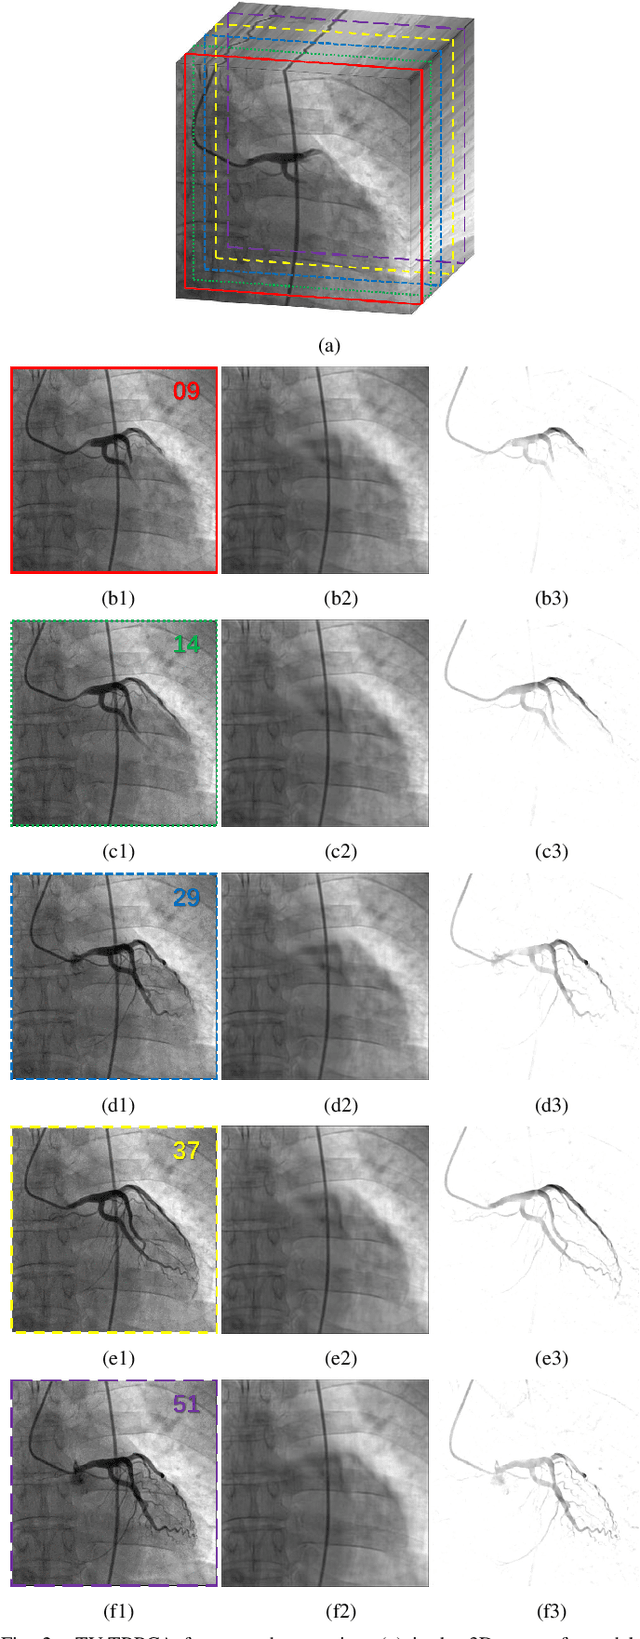

Abstract:The extraction of contrast-filled vessels from X-ray coronary angiography(XCA) image sequence has important clinical significance for intuitively diagnosis and therapy. In this study, XCA image sequence O is regarded as a three-dimensional tensor input, vessel layer H is a sparse tensor, and background layer B is a low-rank tensor. Using tensor nuclear norm(TNN) minimization, a novel method for vessel layer extraction based on tensor robust principal component analysis(TRPCA) is proposed. Furthermore, considering the irregular movement of vessels and the dynamic interference of surrounding irrelevant tissues, the total variation(TV) regularized spatial-temporal constraint is introduced to separate the dynamic background E. Subsequently, for the vessel images with uneven contrast distribution, a two-stage region growth(TSRG) method is utilized for vessel enhancement and segmentation. A global threshold segmentation is used as the pre-processing to obtain the main branch, and the Radon-Like features(RLF) filter is used to enhance and connect broken minor segments, the final vessel mask is constructed by combining the two intermediate results. We evaluated the visibility of TV-TRPCA algorithm for foreground extraction and the accuracy of TSRG algorithm for vessel segmentation on real clinical XCA image sequences and third-party database. Both qualitative and quantitative results verify the superiority of the proposed methods over the existing state-of-the-art approaches.